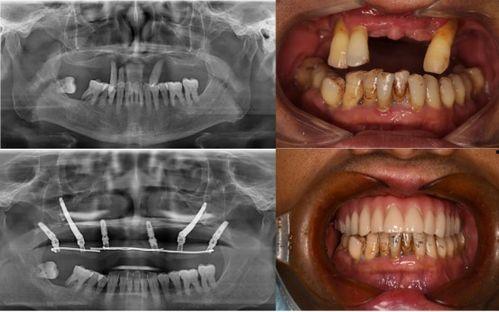

據患者們反映,他們在種植牙的過程中,遇到了種種問題。有的患者表示,醫生在手術過程中操作不規范,導致種植牙失??;有的患者則抱怨,術后恢復期過長,而且效果并不理想。更有甚者,竟然出現了種植牙植入后,牙槽骨吸收的情況。

對于這起事件,口腔醫學專家也給出了自己的看法。他們認為,種植牙是一項高風險的手術,需要醫生具備豐富的經驗和專業的技術。而這家口腔醫院在種植牙過程中出現的問題,反映出我國口腔醫療行業在規范化、專業化方面還存在不少問題。